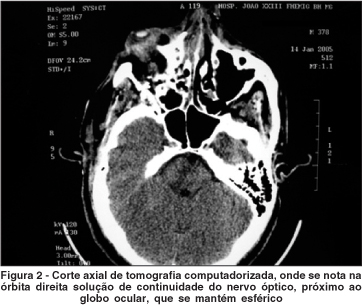

Já na TC notava-se a presença do projétil na órbita direita, hemorragia retrobulbar de médio volume e uma solução de continuidade do nervo óptico, junto ao globo ocular, sugerindo avulsão traumática do mesmo (Figura 2). O bulbo ocular, por sua vez, mantinha sua esfericidade, com bolsões hemorrágicos coroidianos e musculatura extra-ocular íntegra, inserida normalmente.